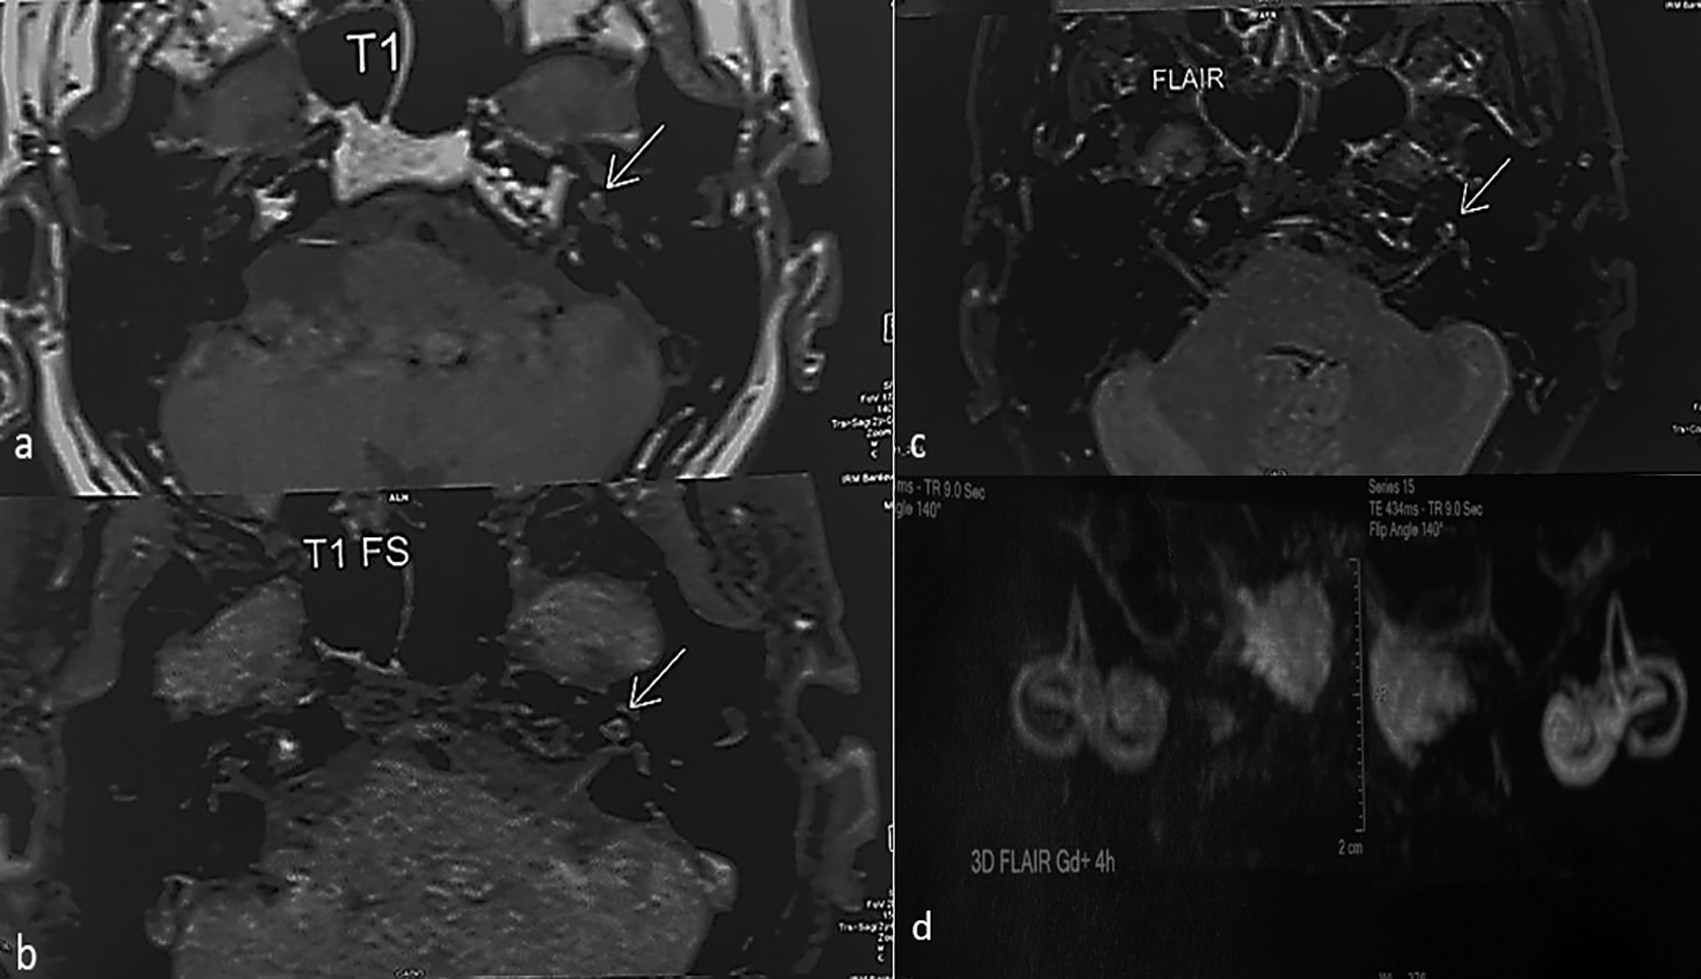

In view of the unilateral sensorineural hearing loss, an additional MRI of the inner ear was performed, including a 3D FLAIR sequence, which showed a high signal intensity in the left cochlea (Figure 2). The patient was diagnosed with a labyrinthine hemorrhage.

MRI allows diagnosis in the form of a spontaneous hypersignal T1, which is not enhanced by gadolinium injection due to the presence of methemoglobin appearing 48 h after the hemorrhagic event. The sequence T2 signal varies according to the age of the hemorrhagic event (hyposignal initially, progressing to isosignal, and then to hypersignal).3 The radiological evolution is variable: persistence of the hypersignal, regression of the images, and normalization or evolution towards sclerosing and ossifying labyrinthitis.5